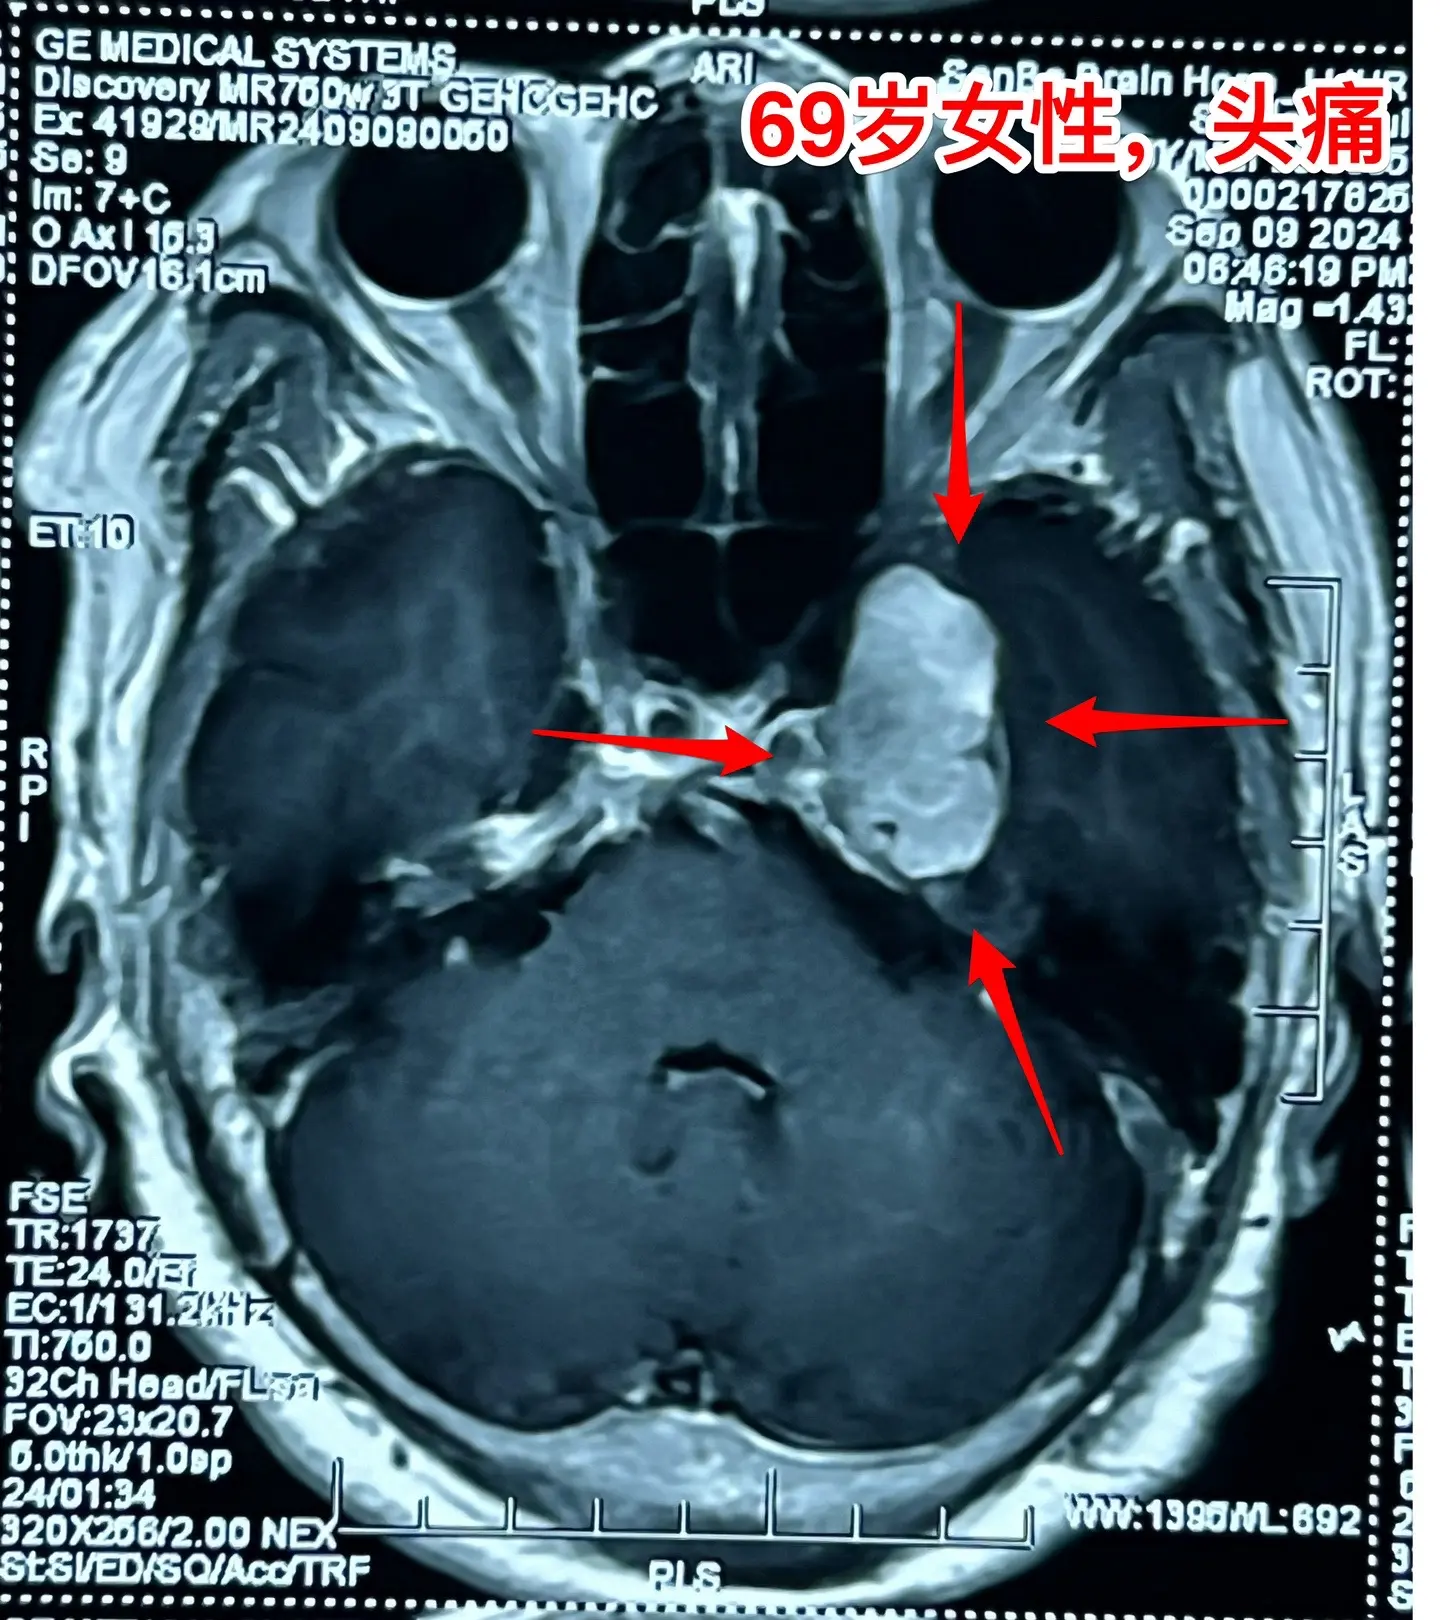

海绵窦区神经鞘瘤,是良性肿瘤。69岁青岛市老太太经常感到头痛,不太剧烈,没有专门去检查。九月份检查脑部磁共振发现左侧海绵窦长了肿瘤。在我院住院后作了强化磁共振,看见左侧海绵窦内有个大肿瘤,见图,考虑是神经鞘瘤,神经鞘瘤是良性肿瘤,如果完全切除了就可以治愈。 老太太有两个女儿,积极要求给她作手术。69岁年龄还是有点大,手术是有风险的! 9月12日下午四点开始进入手术室,手术持续到13日凌晨才结束。手术过程很顺利,肿瘤得到完全切除。今天看见老太太精神比较好,准备下地行走。神经鞘瘤海绵窦